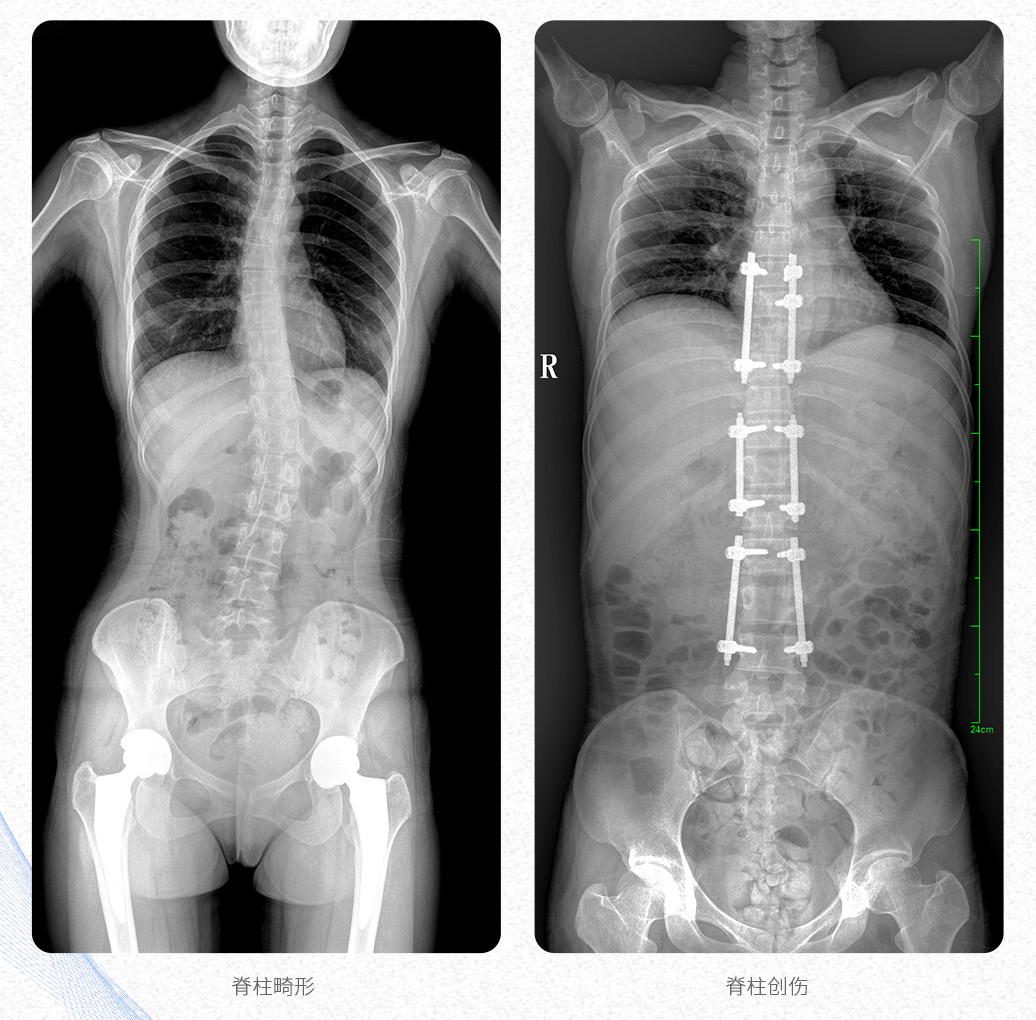

這款大視野U形臂DR的PLX8600數(shù)字化醫(yī)用X射線攝影系統(tǒng)主要應(yīng)用于骨科、創(chuàng)傷科、脊柱正畸科、放射介入科等科室;可供各級醫(yī)院支持全脊柱攝影、雙下肢攝影、脊髓造影、復(fù)雜創(chuàng)傷、人工關(guān)節(jié)置換、關(guān)節(jié)損傷的修復(fù)重建等大視野臨床應(yīng)用。

這款PLX8600數(shù)字化DR采用17"*34"有效視野,一次成像不拼接。相較于多張攝影再軟件拼接的DR設(shè)備,PLX8600動態(tài)平板DR解決了拼接圖像存在密度不均勻,拼接處圖像配準和放大效應(yīng)等問題,給臨床帶來了真正的大視野影像解決方案,高清畫質(zhì),準確成像不失真,可一次性覆蓋全脊柱或雙下肢影像。

【產(chǎn)品臨床圖片】